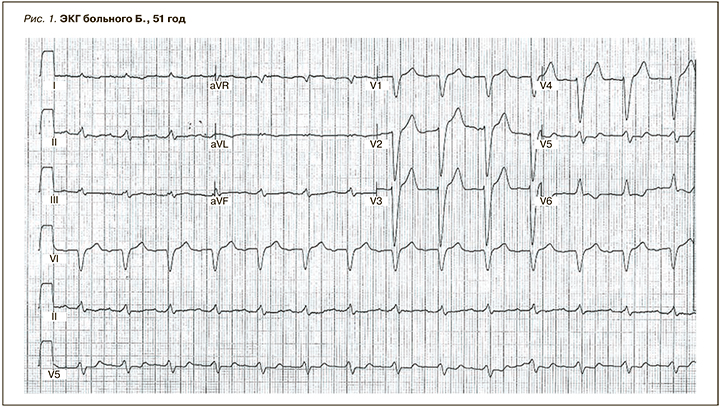

Данные ЭКГ: ритм синусовый, правильный. ЧСС – 72/мин. Низкий вольтаж QRS в стандартных отведениях. Электрическая ось сердца (ЭОС) отклонена влево. PQ – 0,22 c; QRS=0,10 с. Зубец Т отрицательный в I, II, aVL. Обнаружена блокада левой ножки пучка Гиса (рис. 1).